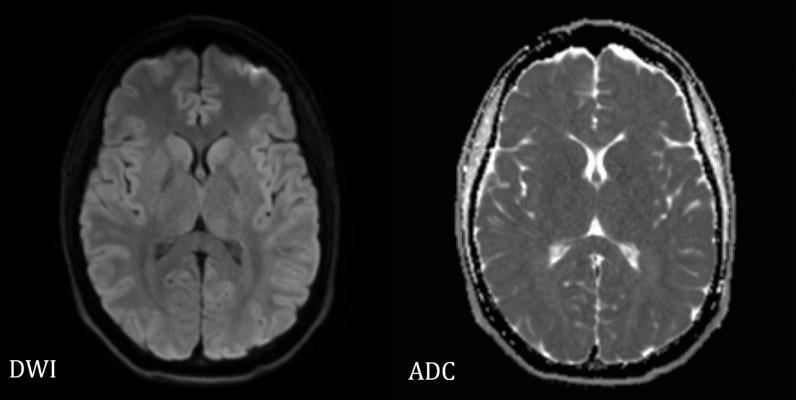

Researchers compared DW MRI, which measures the density of tumors by tracking the movement of water molecules in tissue, to an established technique, fluorine 18 fluorodeoxyglucose positron emission tomography (FDG PET). FDG PET is typically used with computed tomography (CT) scans and measures tumor metabolism after an injection of radioactive glucose.

Both techniques showed significant agreement in tracking tumor response to therapy, raising the possibility that DW MRI might one day be used in place of CT scanning, either together with FDG PET or alone, without the need to inject radioactive glucose. This new approach could reduce radiation exposure by 80% for combined FDG PET/DW MRI and fully eliminate radiation exposure for tumors that can be evaluated with DW MRI only.